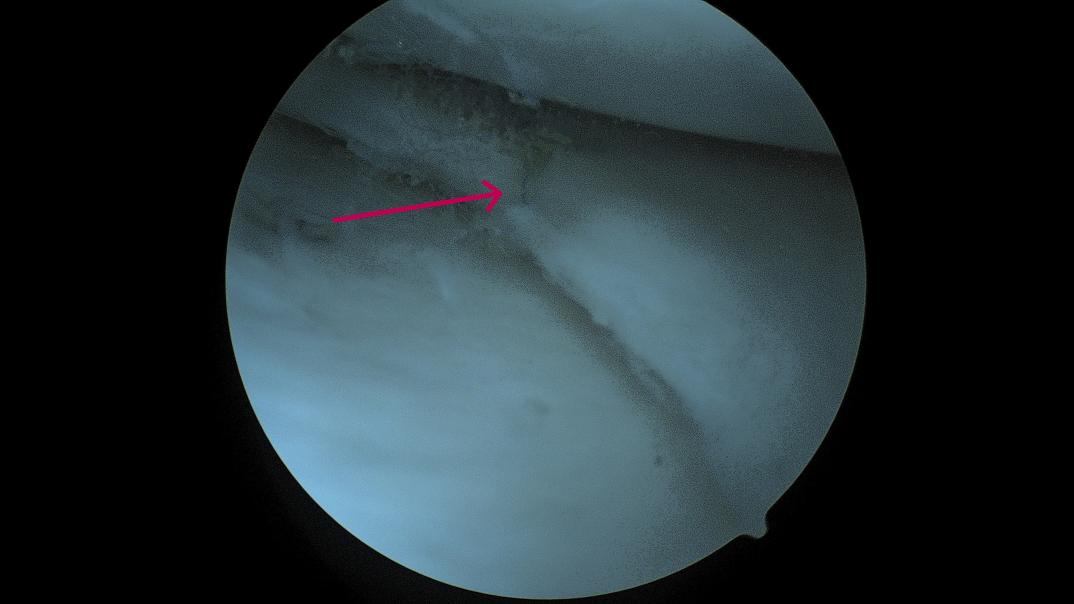

术中发现水平撕裂的半月板(红色箭头所示)

红色箭头所示为应用缝合器技术缝合撕裂后的半月板